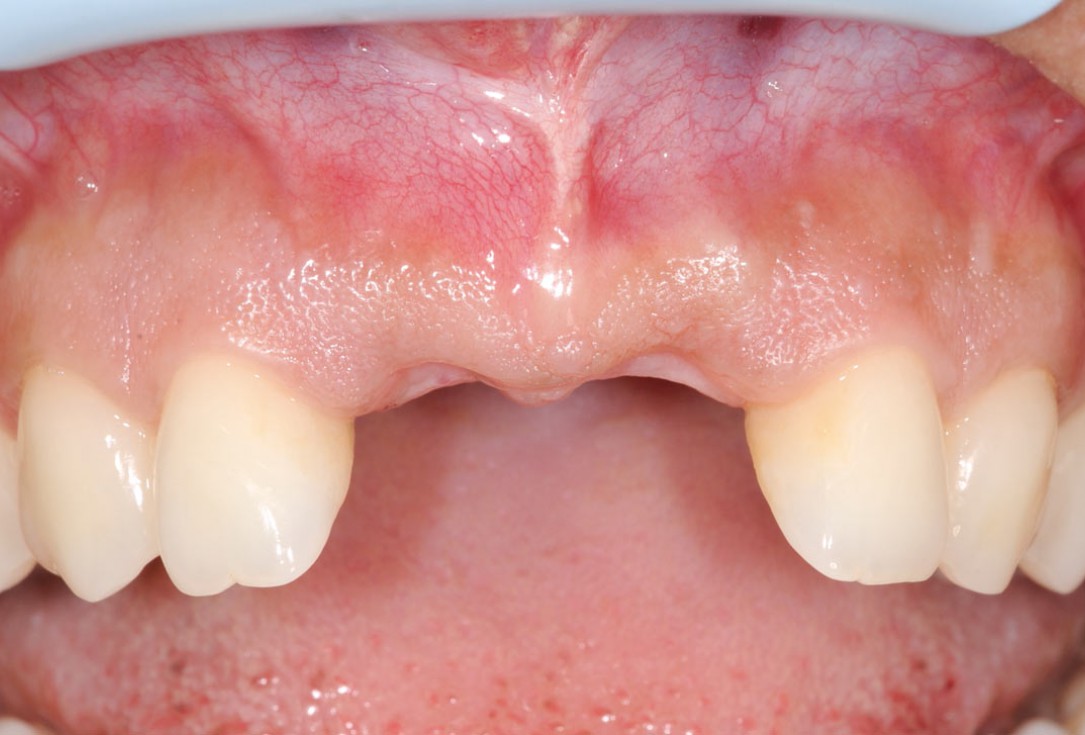

1/26 - Initially bridge retained incisorsBone augmentation in aesthetic zone with maxgraft® bonering - Dr. A. Patel

Initially bridge retained incisors